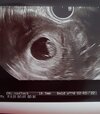

Witam Was wszystkie 😁 ja już po wizycie. Maleństwo rośnie a serducho bije jak oszalałe 😊 życzę wszystkim takich widoków ❤

• 20210524_091950.jpg

20210524_091950.jpg

328,8 KB · Wyświetleń: 131